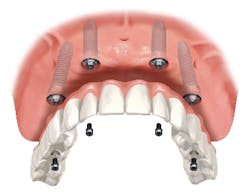

Chewing efficiency is greatly affected by how much of the teeth or bridgework in a given arch is fixed to the jawbone. Just as a person with a wooden leg would not walk as well as a person with a hinged and fitted carbon fiber prosthetic leg, a person with a tissue-supported denture will not chew as efficiently as a person with implant-supported bridges that are fused to the jawbone (figure 1).

A person chewing with upper and lower dentures will only achieve 20% (an average of 30% for the upper denture and 10% for the lower) of the chewing efficiency of a person chewing with a full set of natural teeth, whereas a person chewing with upper and lower implant-supported bridges will achieve 90% chewing efficiency (figure 2). (2)The ability to extract additional nutrients from the food bolus can have a significantly positive impact on a patient’s overall health. Studies have tied the use of implant-supported bridges versus dentures to an increase in life expectancy of seven years. (3) To maximize a patient’s health and reduce future costs, it is important to use a fixed prosthesis versus a removable one.